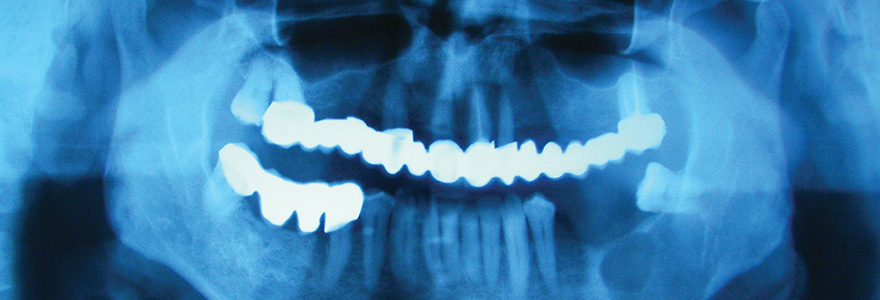

The field of Oral Biology and Medicine focuses on cellular and subcellular mechanisms in healing and malignant transformation in oral and maxillofacial tissues. Researchers in this cluster are investigating gingival healing and fibrosis, based on an interdisciplinary approach involving maintenance of functional tissues, cellular and molecular mechanisms involved in connective tissue repair. In addition, the role of diagnostic and prognostic biomarkers in oral epithelial dysplasia and cancer transformation, and in selected jaw lesions, are also examined.